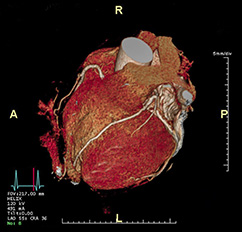

Die koronare Herzerkrankung (KHK) ist eine der häufigsten Erkrankungen in der westlichen Welt. Bei dieser Erkrankung führen Cholesterin- und Kalkablagerungen an der Gefäßwand (Arteriosklerose) zur Verengung der Herzkranzgefäße (Koronararterien). Diese Engstellen (Stenosen) vermindern die Blutversorgung des Herzmuskels. Kommt es mit dem Fortschreiten der KHK zum Gefäßverschluss, entsteht ein Herzinfarkt. Die Computertomographie des Herzens (Kardio-CT) ist nach Leitlinien die geeignete Methode, eine koronare Herzkrankheit zu erkennen oder diese mit an Sicherheit grenzender Wahrscheinlichkeit auszuschließen.

Neben der Abbildung der Herzkranzgefäße mit der Kontrastmittelgabe in die Vene führen wir auch immer einen Scan ohne Kontrastmittel für das sogenanntes Kalzium-Scoring durchgeführt. Dabei wird gemessen, wieviel Kalk in Ihren Herzgefäßen eingelagert ist. Das Ausmaß der Verkalkungen der Koronargefäße wird als sogenannter Kalzium-Score (auch Agatston-Score genannt) wiedergegeben. Diese Messung allein kann für die statistische Abschätzung Ihres individuellen Risikos, eine Herzgefäßerkrankung zu haben und dadurch relevant zu erkranken, wichtige Ergebnisse liefern. Wenn bei Ihnen eine Kontraindikation (Gegenanzeige)für die Kontrastmittel-gestützte Darstellung der Herzkranzgefäße besteht, kann nur dieser Kalzium-Score-Scan durchgeführt werden. Wenn Sie sehr viel Kalk in Ihren Koronargefäßen haben, kann dies die Bewertung des Ausmaßes möglicher Engstellen der Herzkranzgefäße durch die Kontrastmittel-gestützte CT-Untersuchung erschweren. Wir nehmen dann im Befund dazu und zu den weiteren Konsequenzen Stellung. Unsere Befundung erfolgt standardisiert nach CAD-RADS 2.0, einer Befundungsleitlinie, auf die sich die Fachgesellschaften für Kardiologie und Radiologie verständigt haben.